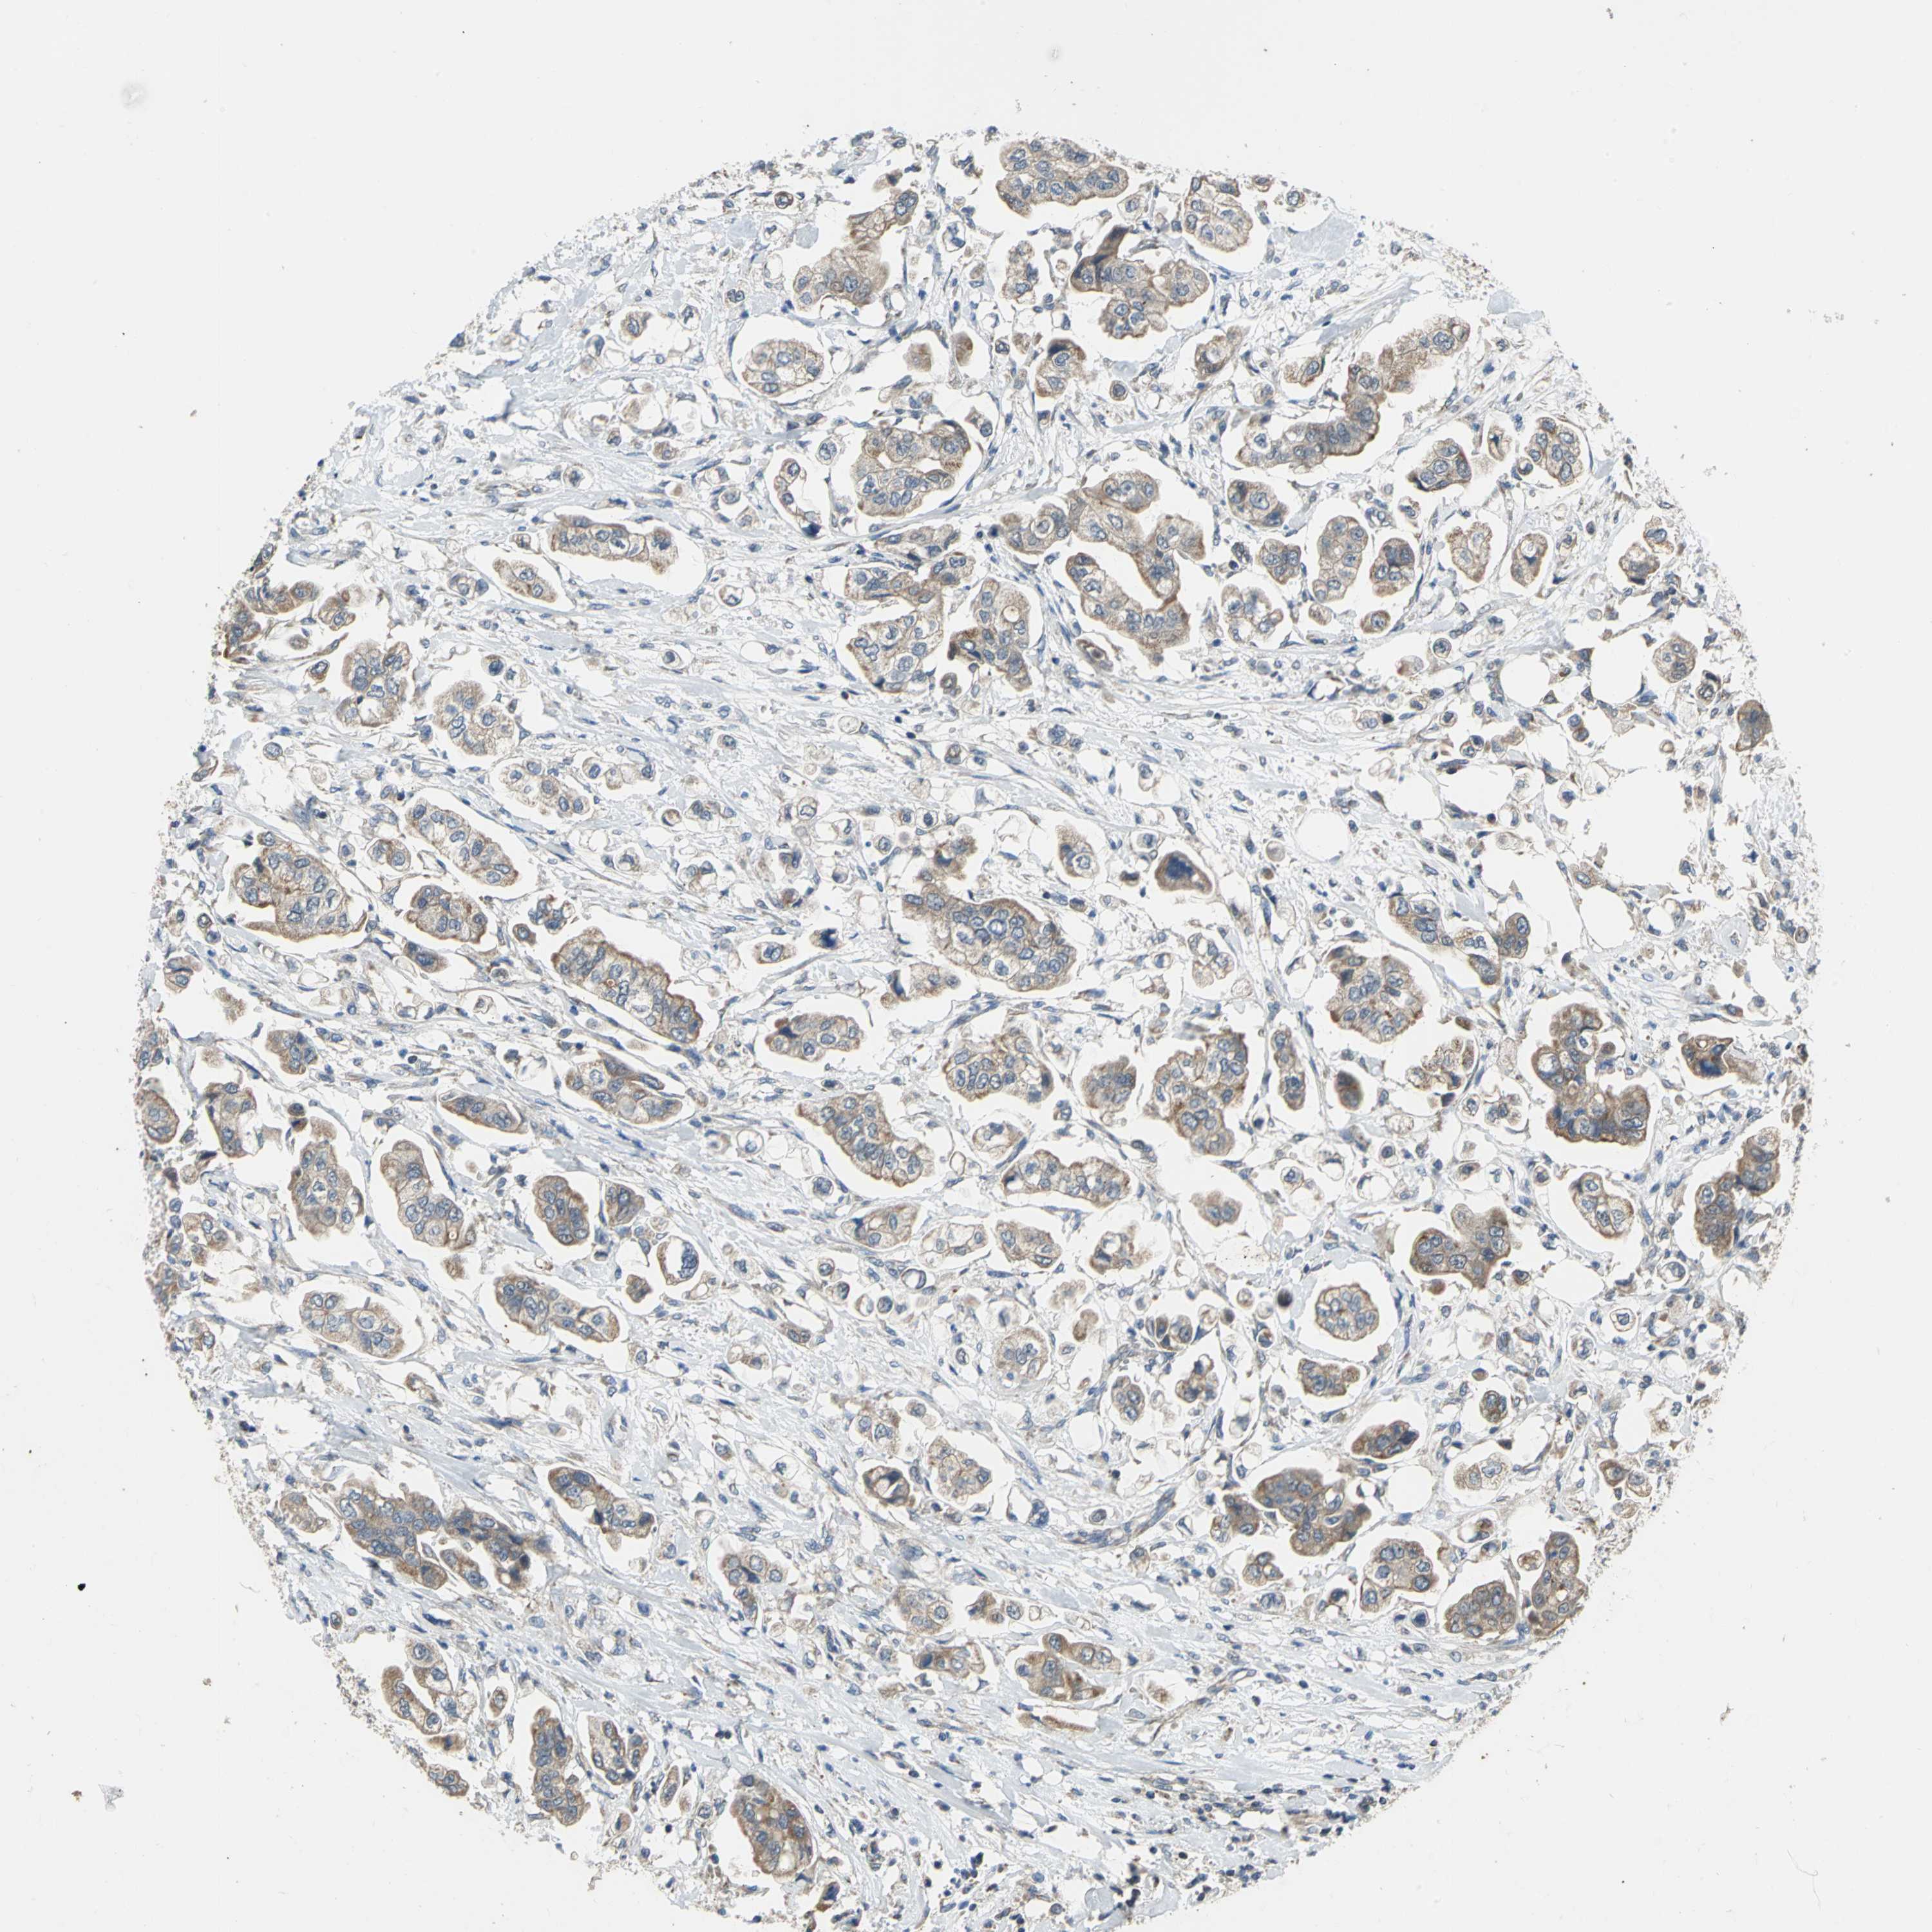

STOMACH CANCER - Protein expressioni

A mouse-over function shows sample information and annotation data. Click on an image to view it in a full screen mode. Samples can be filtered based on level of antibody staining by selecting one or several of the following categories: high, medium, low and not detected. The assay and annotation is described here.

Note that samples used for immunohistochemistry by the Human Protein Atlas do not correspond to samples in the TCGA dataset.

Antibody stainingi

Antibody staining in the annotated cell types in the current human tissue is reported as not detected, low, medium, or high, based on conventional immunohistochemistry profiling in selected tissues. This score is based on the combination of the staining intensity and fraction of stained cells.

Each image is clickable and will lead to virtual microscopy that enables deeper exploration of all samples and also displays staining intensity scores, fraction scores and subcellular localization as well as patient and tissue information for each sample.

Antibody HPA005853

Staining

High

Medium

Low

Not detected

Intensity

Strong

Moderate

Weak

Negative

Quantity

>75%

75%-25%

<25%

None

Location

Nuclear

Cytoplasmic/membranous

Cytoplasmic/membranous,nuclear

Adenocarcinoma, NOS

Adenocarcinoma, High grade